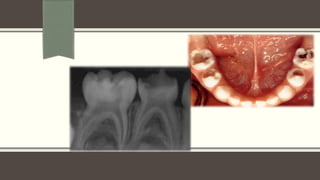

CASE SELECTION : WATERHOUSE ET AL (2000 )

Teeth with deep DC ( x ray – approximating to pulp)

Teeth should be restorable after procedure

Absence of symptoms of advanced pulpal inflammation

Absence of Cl signs or sympytoms

Absence of Cl & x-ray signs of pulpal necrosis

Hamorrhage should stop within 5 min